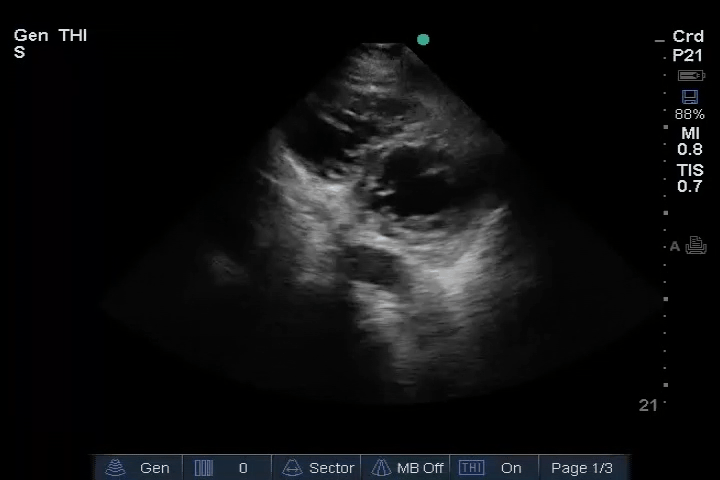

13_Heart_PSAX – Dilated RV

Heart: Dilated right ventricle (RV), most clearly visualized in the PSAX view. An embolus is visible in the right atrium (RA).